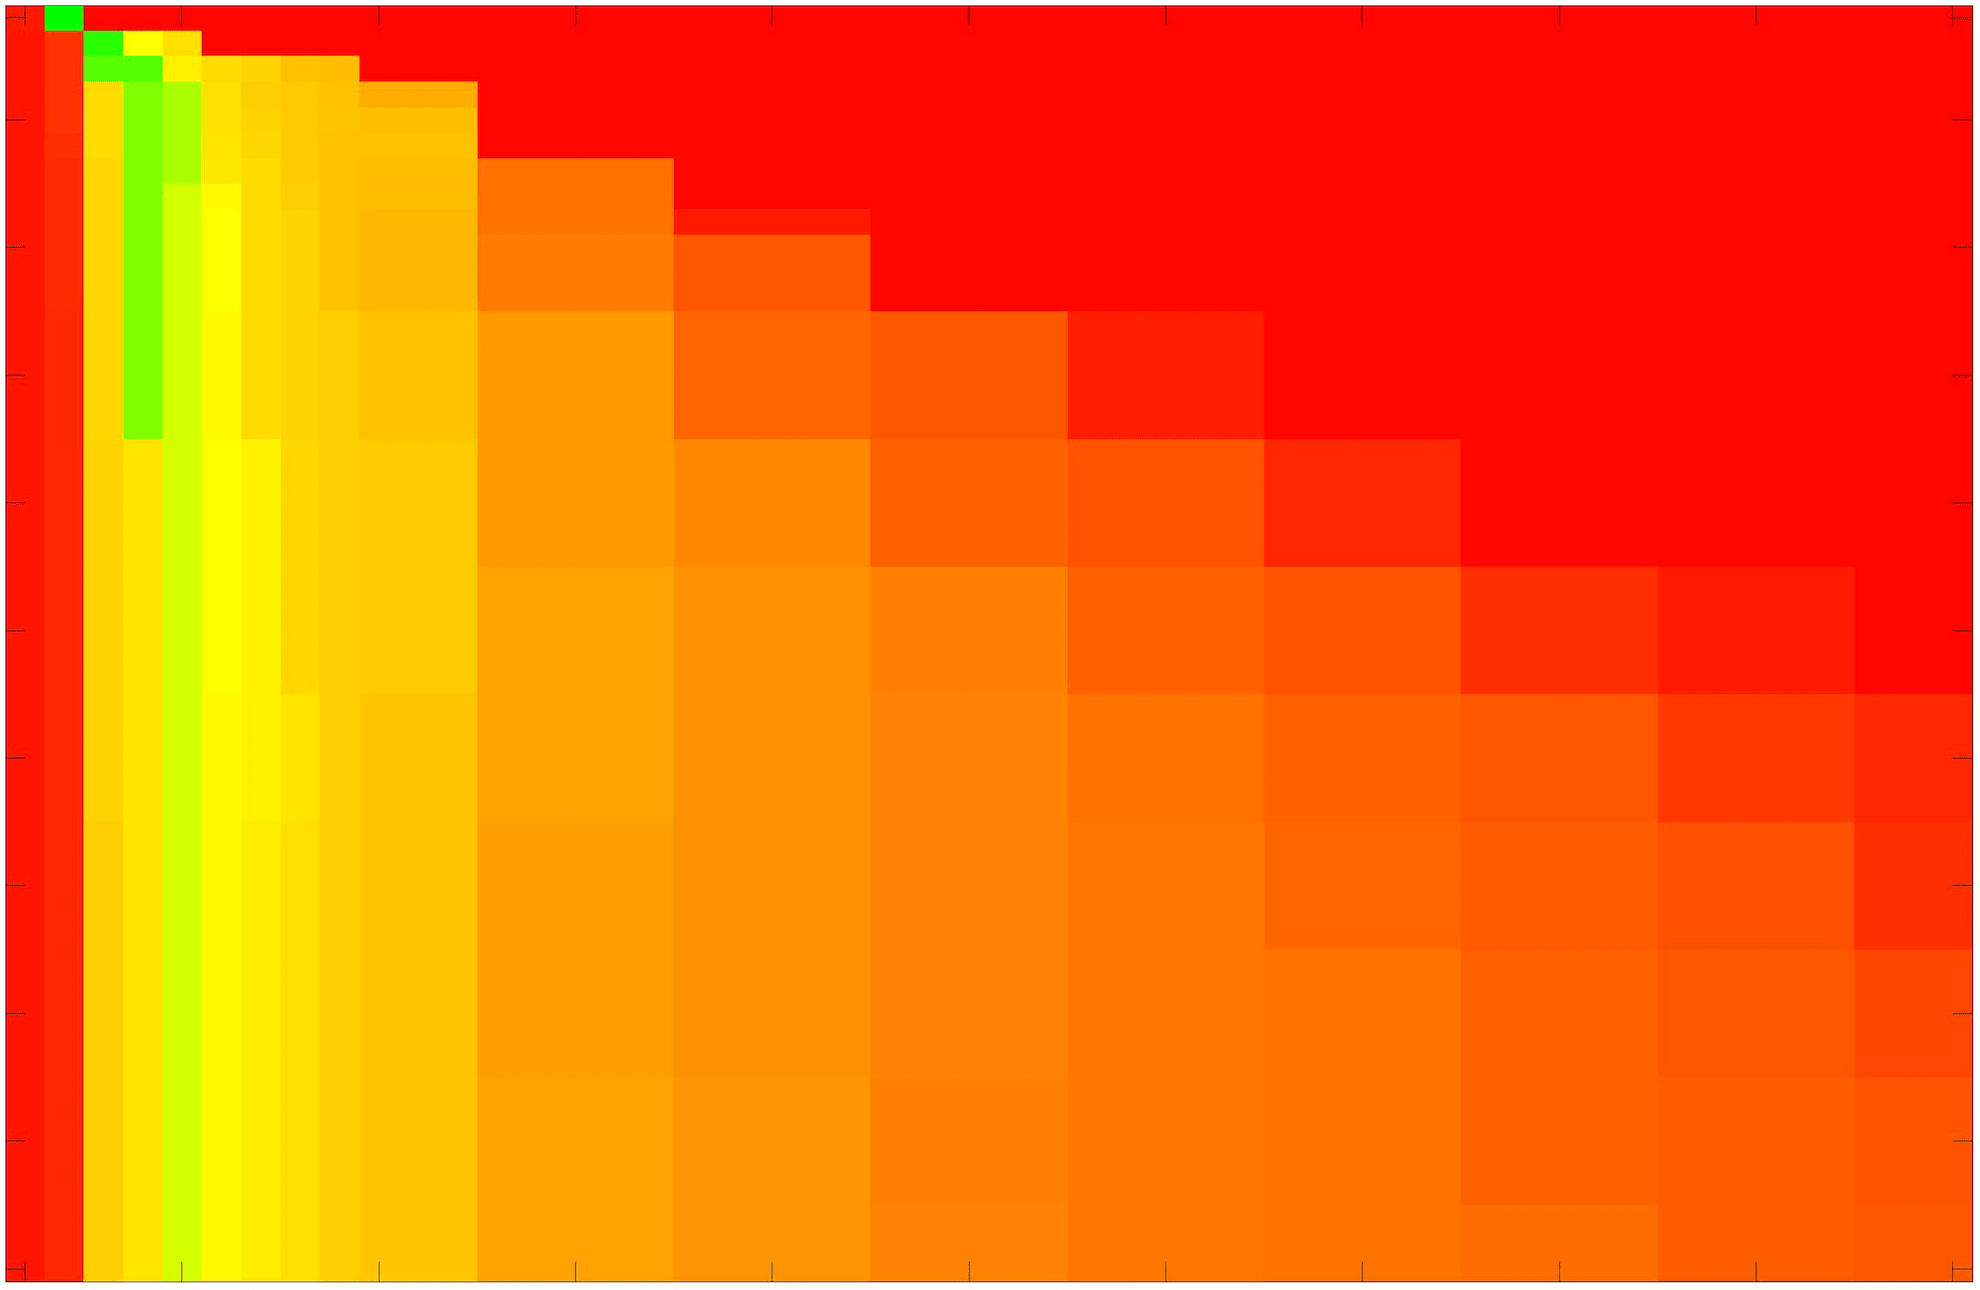

where refers to the number of points in the enclosed region. This takes values in the range , with higher TC values indicating a more accurate segmentation. In the following we will represent accuracy visually from red () to green (), with the intermediate scaling of colours used shown in Fig. 8. This will be particularly relevant in §7.2.

The TC values for the parameter sets are presented as heatmaps in Figs. 11–13. A heatmap is a convenient way to display accuracy results for hundreds of tests concisely. In Fig. 9 we give an example heatmap with the same axes used for those in Figs. 11–13. For each of the combinations of parameter values we give the TC value of the segmentation result and represent it by the appropriate colour. The corresponding colour scale is shown in Fig. 8. Qualitatively, the more green areas of the heatmap the more accurate the model is for a wider set of parameters. Example results for Test Image 5 when varying (with ) for the proposed model are given in Fig. 10. Here it can be seen what each accuracy result corresponds to visually.

Note. The axes have been removed from the heatmaps in Figs. 11–13 for presentational clarity. However, to be explicit, the axes used in all heatmaps are the same as those in Fig. 9.

Synthetic Images. These results are presented in Fig. 11. For Test Images 1–2 we see poor parameter robustness from all competing models, except for GAV which performs reasonably well. However, the proposed model has minimal parameter sensitivity for these images, with good results achieved for almost every combination of values tested. For Test Image 3 all models have a reasonable parameter range (except for RSF), however the proposed model gives better quality results for a wider parameter range. The other models achieve reasonable results here as the foreground intensity of the ground truth is greater than the background , whereas for Test Images 1–2 they are equal . These results highlight the key advantage of the proposed model.

Real Images. In Fig 12 we present results for Test Images 4–6. Here, the proposed model performs in a similar way to its competitors because these images are more typical selective segmentation problems in the sense that there is a clear distinction between the foreground and background intensities. In particular, the values in each case are: Test Image 4 , Test Image 5 , and Test Image 6 . It can be seen that the proposed model is competitive compared to previous approaches. The performance is quite poor for Test Image 5, but is arguably still the best for this challenging case. In Fig. 13 we present results for Test Images 7–9. Here the proposed model outperforms previous approaches significantly for each image. This is mainly due to the type of image considered. Specifically, the true intensities are: Test Image 7 , Test Image 8 , and Test Image 9 . The proposed model is capable of achieving results where , with other models failing completely in these cases.